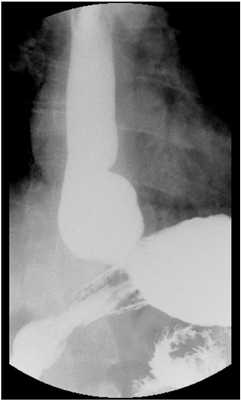

Пальпация области шеи, рентгенография пищевода простая и контрастная. Контрастные инородные тела видны при обзорной рентгеноскопии и рентгенографии грудной клетки. При подозрении на заглатывание неконтрастного инородного тела проводят исследование с контрастным веществом (больному дают одну чайную или десертную ложку густой бариевой взвеси, затем он делает 2-3 глотка воды, в норме вода смывает барий, но при наличии инородного тела часть контрастного вещества задерживается на нем - способ СВ. Ивановой-Подобед). При локализации инородного тела в шейном отделе пищевода выполняют боковую рентгенографию гортаноглотки в проекции Г.М. Земцова, позволяющую также диагностировать сопутствующие воспалительные изменения околопищеводной области. При локализации неконтрастных инородных тел в грудном и диафрагмальном отделах пищевода определяют "симптом слепка" - маятникообразные движения контрастной взвеси - движение вверх при глотании фиксированного на инородном теле контраста.

С точки зрения врача рентгенолога обычного рентгеновского кабинета, оборудованного первым рабочим местом (скопией) ожидаемая скеалогическая картина, которая может иметь место, это перераспределение введенного рентген-контрастного вещества из желудка в пищевод, как самопроизвольное, так и спровоцированное в отсутствии позывов на рвоту. В данном случае можно говорить лишь о забросе содержимого желудка в пищевод [6]: гастроэзофагальный рефлюкс (ГЭР).

Описание [1,3,5,6]:

Пациент доставляется в рентгеновский кабинет натощак, перед очередным кормлением. Проводится предварительное просвечивание органов грудной клетки и брюшной полости.

Далее необходимо заполнить желудок. Заполнение желудка может осуществляться как через зонд (с соблюдением правил выполнения постановки), так и самостоятельно, из рожка, стакана.

Объём вводимого контраста должен соответствовать объёму разового кормления, детям до 3-х месяцев вводится 40-80 мл, старше от 60 до 200 мл. Давать свыше 200 мл, независимо от возраста нецелесообразно. На этом этапе, при укладывании пациента, или в результате ротации в некоторых случаях может регистрироваться ГЭР.

Далее выполняется осмотр желудка, двенадцатиперстной кишки (ДПК): оценивается анатомия и топография, скорость эвакуации из желудка, скорость пробега по ДПК, наличие препятствий пассажу, дискинезии, проводится пальпация, для ускорения пассажа и как провоцирующий фактор.

Провокационные пробы включают в себя ротацию пациента, умеренное давление на живот, напряжение мышц живота (кашель, натуживание, приподнимание пациентом ног). Положительной (у младенцев) считается проба, при которой в результате давления на живот в течении 30 сек. и сразу после этого отмечается, как минимум, два эпизода заброса контрастного вещества из желудка в пищевод. При этом рвота в расчёт не принимается. Рвота: сложный рефлекторный акт, характеризующийся сокращением желудка, раскрытием нижнего и верхнего пищеводных сфинктеров с выбросом контраста наружу.